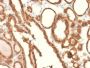

Epitope of this MAb is mapped between aa 202-212 of EGP40, which is a 40-43 kDa transmembrane epithelial glycoprotein, also identified as epithelial specific antigen (ESA), or epithelial cellular adhesion molecule (Ep-CAM). It is expressed on baso-lateral cell surface in most simple epithelia and a vast majority of carcinomas. Antibody to Ep-CAM has been used to distinguish adenocarcinoma from pleural mesothelioma and hepatocellular carcinoma. This antibody is also useful in distinguishing serous carcinomas of the ovary from mesothelioma.

IHC, FFPE (verified), WB (verified)

Higher concentration may be required for direct detection using primary antibody conjugates than for indirect detection with secondary antibody|Immunohistology (formalin): 0.5-1 ug/mL for 30 minutes at RT|Staining of formalin-fixed tissues requires boiling tissue sections in 10 mM citrate buffer, pH 6.0, for 10-20 minutes followed by cooling at RT for 20 minutes|Optimal dilution for a specific application should be determined by user